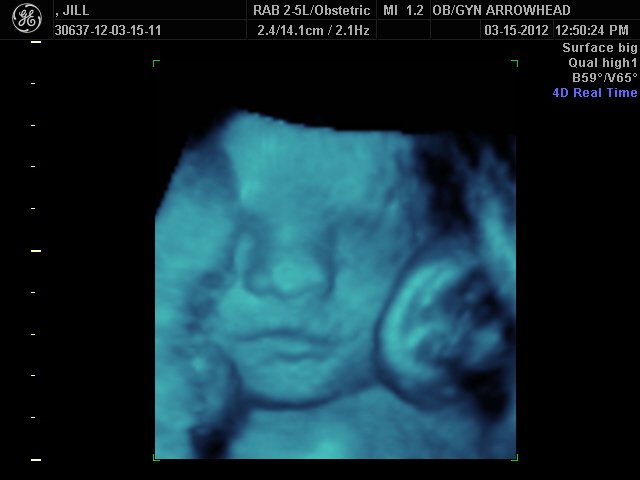

We offer complimentary 3D/4D Ultrasounds to all our OB patients around 30 weeks! The following photos are some examples of our work, shown with permission from our patients.